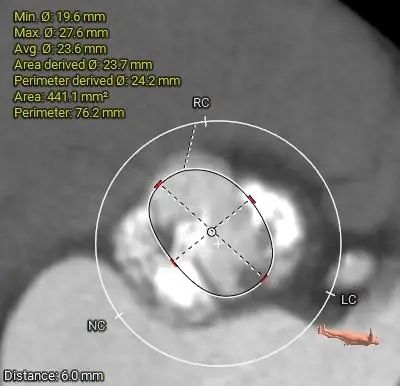

ANNULUS

6mm SUPRA ANNULUS